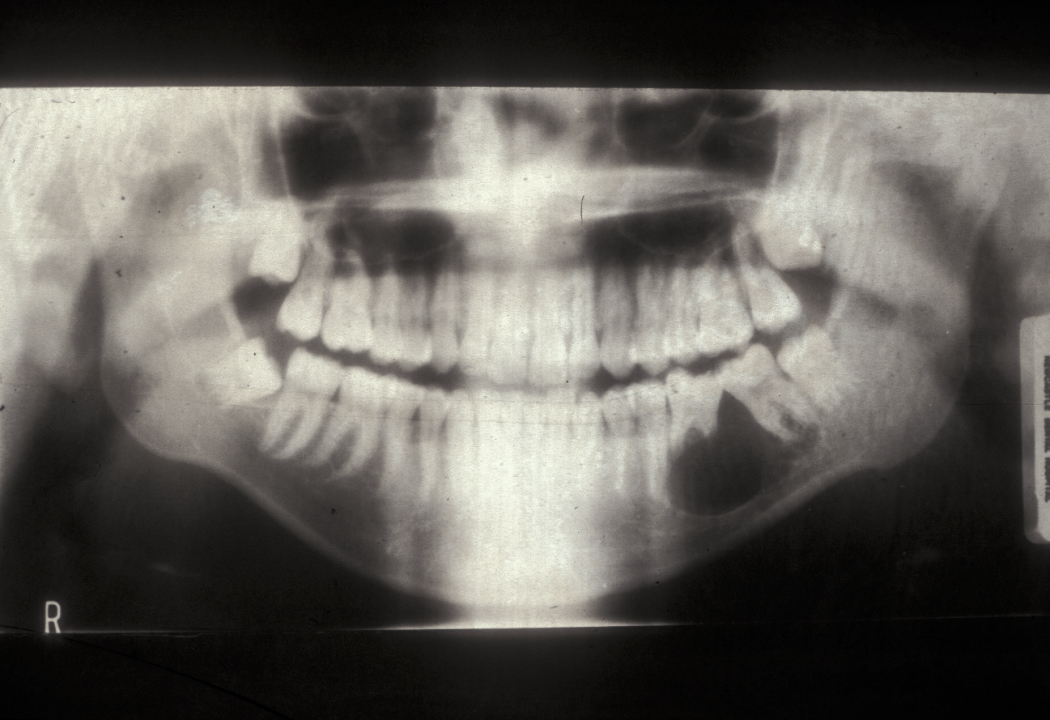

This condition has a number of different names and it occurs in approximately 3 % of routine tooth extractions, and up to 20 % of surgical tooth extractions. Figure 1 shows a dry socket, Figure 2 shows the radiograph of a severe case of dry socket.

Figure 1: Dry socket, a painful osteitis (bone inflammation) of the tooth socket.

Figure 2: Radiograph of a severe case of dry socket, leading to sequestration (formation of a dead piece of bone).